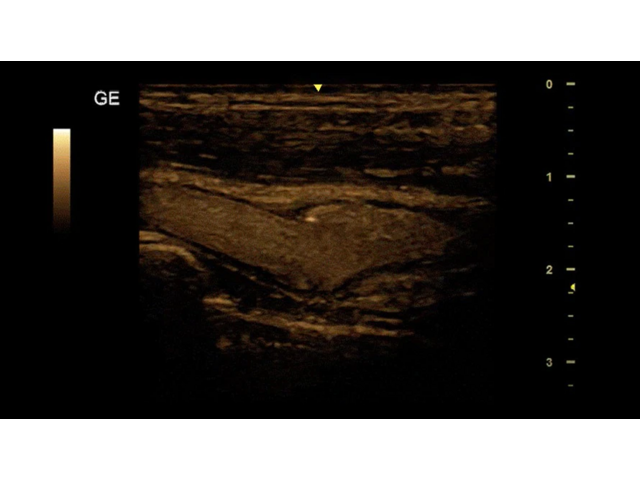

Ультразвуковой сканер GE Versana Essential отличается высокой точностью и мобильностью. Он широко используется при обследовании скелетно-мышечной системы и является незаменимым инструментом в урологии, гинекологии, педиатрии и общей радиологии.

Благодаря передовым технологиям и инновационным функциям, ультразвуковой сканер GE Versana Essential обеспечивает высокую четкость и детализацию получаемых изображений. Он позволяет врачам проводить диагностику и оценку состояния тканей и органов с высокой точностью, что способствует более точным и эффективным клиническим решениям.